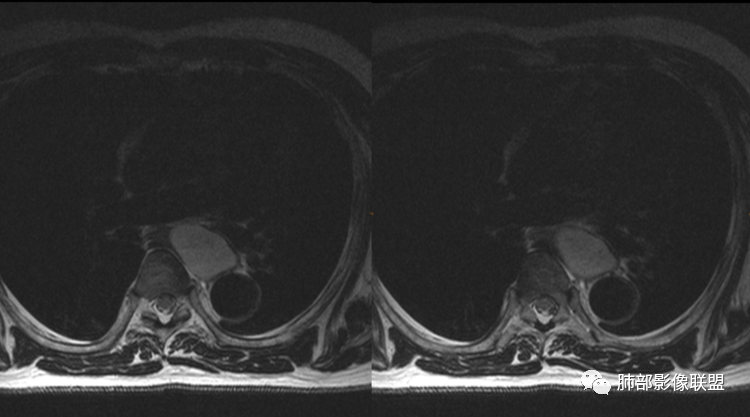

男性,43岁,体检发现后纵隔占位,边缘光整,CT示密度均匀,周围组织受压移位,无钙化囊变及脂肪组织,增强未见明显强化。MRI:T1示肿块信号较肌肉高,T2不均匀高信号。考虑为良性病变,第一是神经节细胞瘤,其次是支气管源性囊肿。

中年男性,无症状,后纵隔肿块,长径大矢状位于横径,质地偏软,塑形,等t1稍长t2,比较均质,增强轻微强化,与脊柱,主动脉,食管脂肪间隙存在,部分层面与脊柱相贴,骨质无改变,周围无肿大淋巴结,考虑神经源性肿瘤,节细胞神经瘤可能大,鉴别心包斜窦,淋巴瘤,淋巴管囊肿。